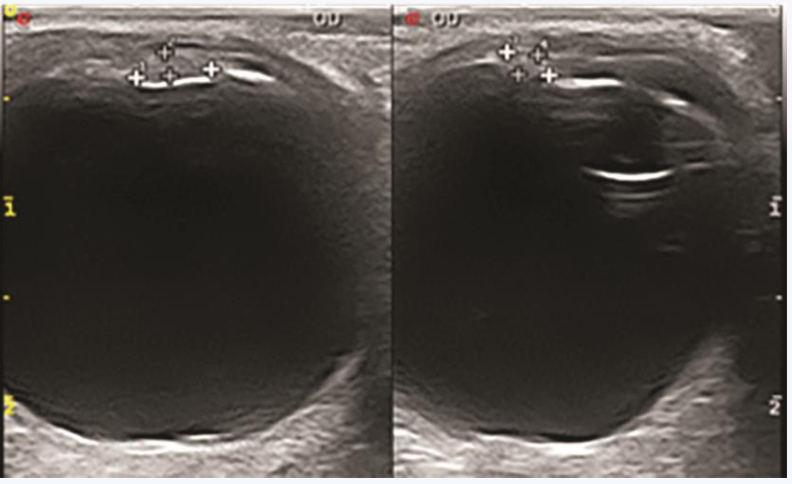

1周后患者复诊,查体:视力右眼0.7,左眼1.0,眼压右眼11mmHg,左眼15mmHg。右眼角膜清,前房中深,瞳孔圆,直径约3mm,对光反射存在,颞上方虹膜实性占位性病变大小未见明显改变,肿物表面出血较前吸收,色素脱失较前加重,前房白色絮状渗出明显吸收(图4)。右眼眼底及左眼查体同前。眼部UBM示右眼颞上方虹膜可见不规则形实性病变,大小约2.88mm×3.80mm×1.90mm,边界尚清晰,内回声不均匀,部分病变与角膜及晶状体前囊相贴,颞侧及下方房角内可见团条状回声,部分与虹膜相连;CDI示右眼颞上方虹膜实性占位性病变大小约3.5mm×2.3mm×1.4mm,边界欠均匀,内回声不均匀,CDFI病变内未探及明显血流信号;眼眶MRI示颞侧虹膜区见条状等T1、略短T2信号影,边缘不清,大小约2mm,增强后可见强化;胸部X线、血尿常规、CRP、生化常规、凝血四项、免疫四项、T-SPOT结核杆菌γ-干扰素释放试验、抗链O、抗核抗体(ANA)、TORCH特异性抗体检查均未见明显异常。

图2 UBM示右眼颞上方虹膜可见不规则形实性病变与角膜及晶状体前囊相贴